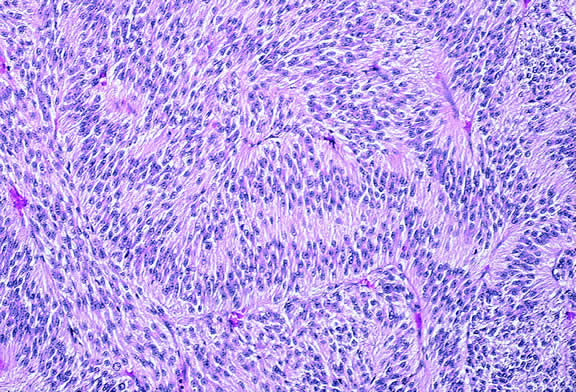

Occasionally, the spindle cells in a melanoma are arranged in a radial fashion around vessel or fibrovascular septa (vasocentric pattern), or the nuclei form rows that resemble the Verocay bodies or Antoni A pattern seen in schwannoma (Verocay pattern). Melanomas are called fascicular if these patterns dominate5 (Fig. 36). Fascicular melanoma was a category in Callender's initial classification90 that was dropped from McLean's 1983 modification.5,91

Fig. 36. Fascicular melanoma. This amelanotic melanoma has a striking fascicular appearance. The nuclei of its constituent spindle cells form rows that resemble the Antoni A pattern seen in schwannoma. The fascicular category of uveal melanoma has been removed from the modern revision of Callender's classification because cellular arrangement does not appear to affect prognosis. (Hematoxylin-eosin, × 50.)